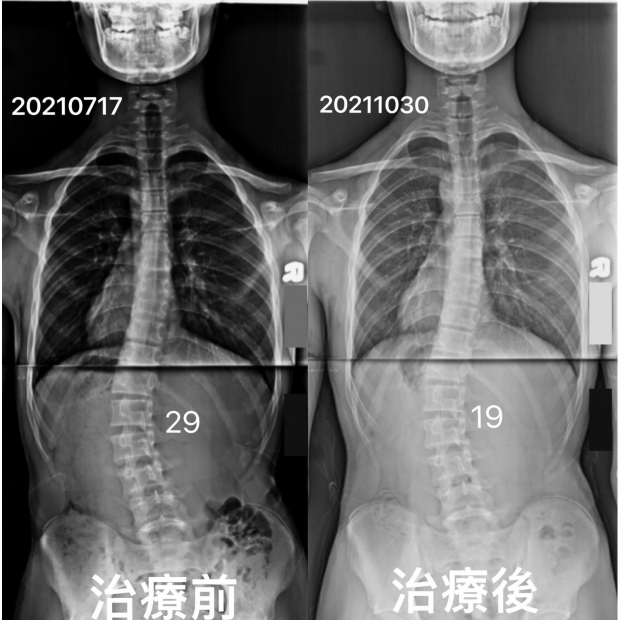

14歲側彎男孩矯正案例,積極溝通 及時回饋 讓我們更好得幫助您挺直腰桿,平衡體態14歲側彎男孩矯正案例,積極溝通 及時回饋 讓我們更好得幫助您挺直腰桿,平衡體態

14歲男孩,脊椎側彎29度,一個療程後改善至19度 -